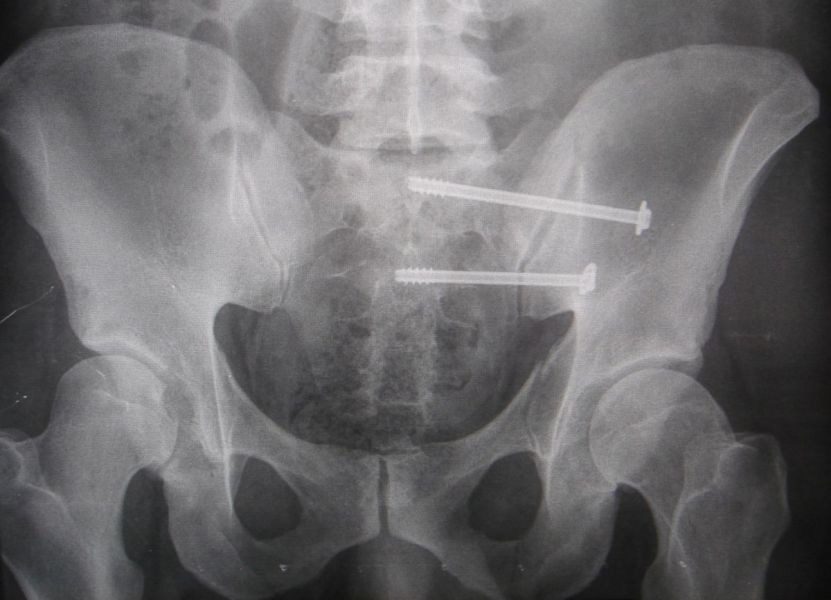

1. Pelvic fracture involved sacrum caused by lateral compression in a 25-year-old male.

Treatment: Percutaneous fixation with two sacroiliac screws

I. Before surgery, axial view of CT scan showing fracture of sacrum on the left side II. Post-surgery, anteroposterior x-ray of pelvis with the two sacroiliac screws